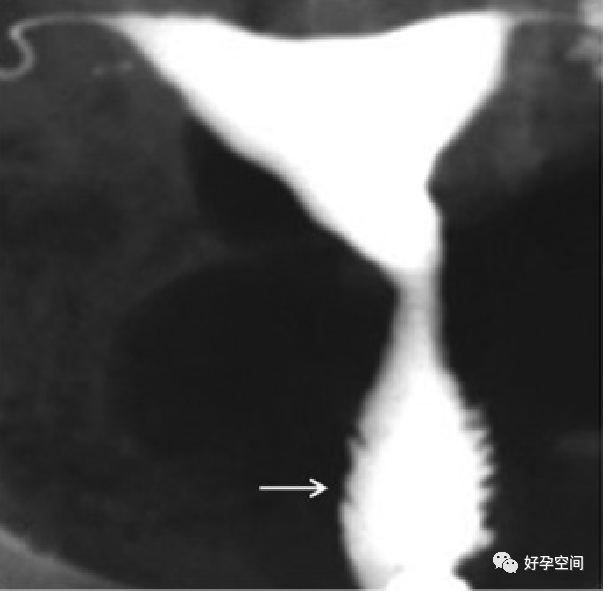

4、正常宫颈管及变异:子宫颈管的变异很大,子宫颈管的形状分为(a) 圆柱形、(b)漏斗形、(c) 球形、(d) 梨形、(e)纺锤形五型。